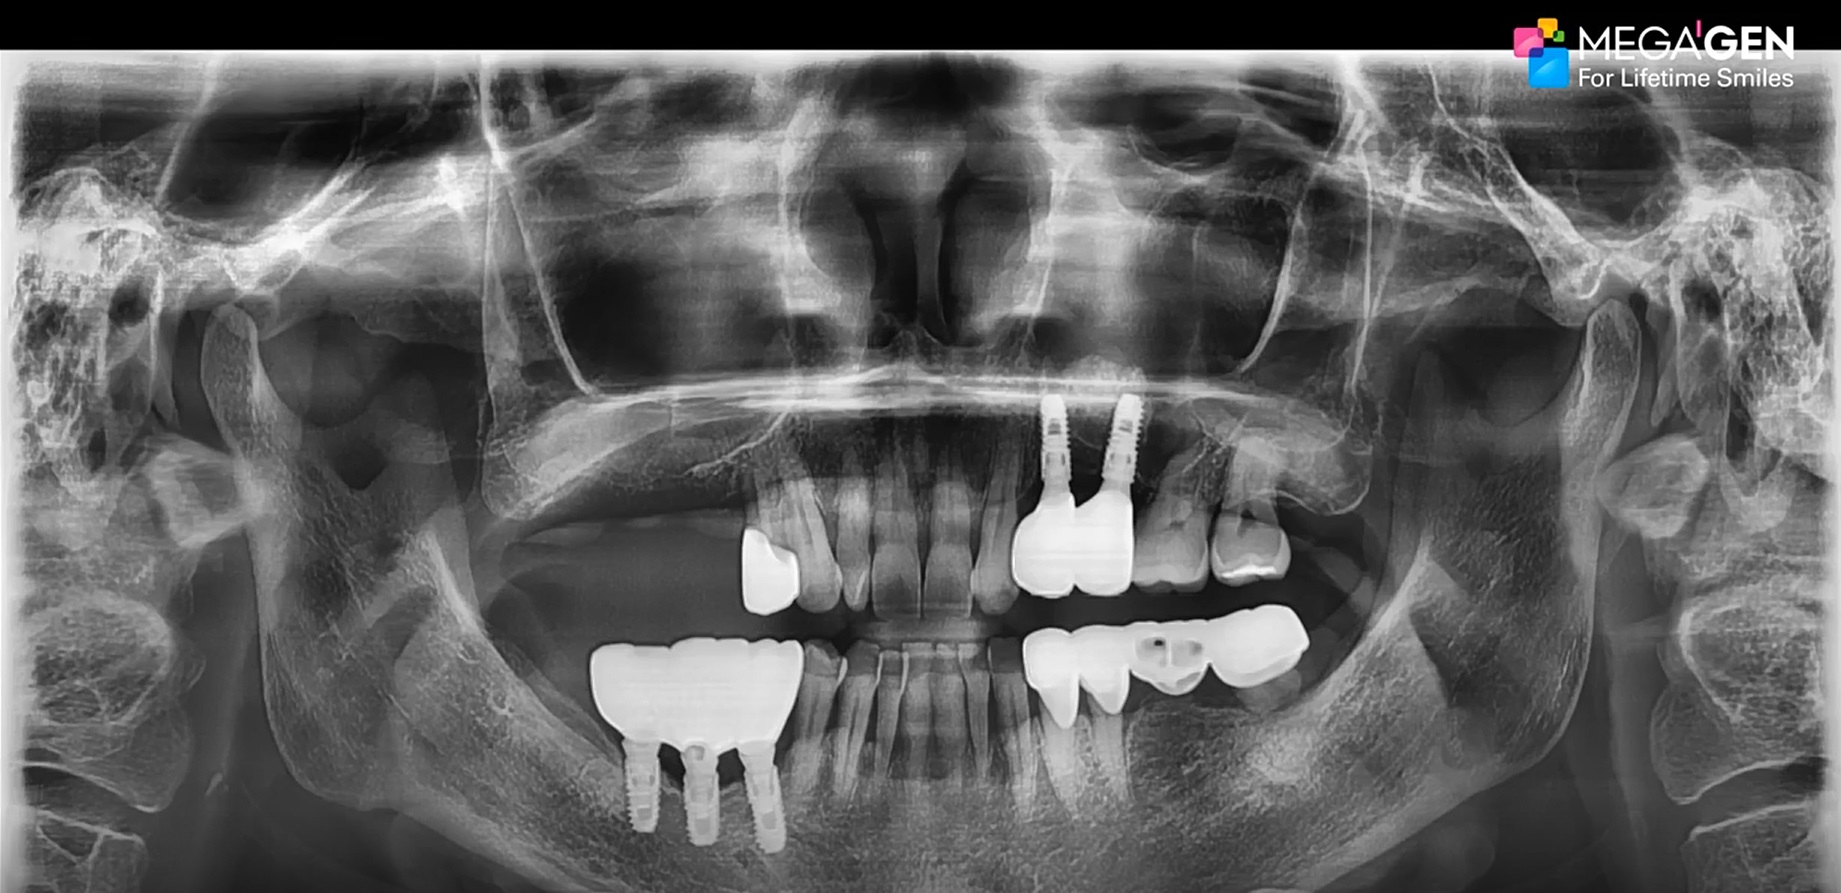

How to get a reliable ISQ!

#23,#24,#25,#26,#27,Aesthetic zone,AnyRidge,Digital,Digital Guided Surgery,Edentulous,Flapless,Immediate loading,Immediate Placement,Maxillary Posterior,MEGA ISQ,R2GATE,R2GATE Guide,R2GATE Surgical Kit(AnyRidge),video